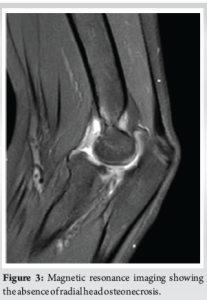

Six months after traumatism, magnetic resonance imaging was performed and showed no sign of avascular necrosis of the radial head (Fig. 3). The range of motion was still limited at that time, with a 30° lack of elbow extension and pronation limited to 20°. Radiograph showed persisting slight anterior subluxation of the radial head. A night dynamic elbow extension brace (Ultraflex) was applied to improve extension.